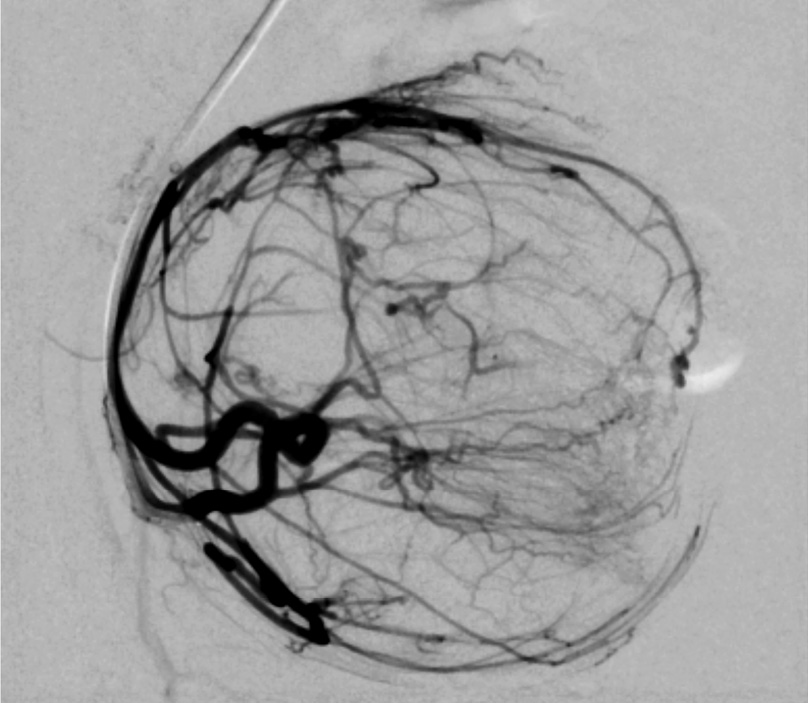

Рис. 2. Клинический пример №1. Ангиограмма правой маточной артерии до ЭМА. / Fig. 2. Clinical case 1. Angiogram of the right uterine artery before UAE.

Рис. 3. Клинический пример №1. Ангиограмма левой маточной артерии до ЭМА. / Fig. 3. Clinical case 1. Angiogram of the left uterine artery before UAE.

Выполнены пункция и катетеризация правой лучевой артерии в ретроградном направлении. Далее катетером выполнена селективная катетеризация правой и левой маточных артерий. Выявлена миома матки больших размеров с выраженным перифиброидным сплетением. При проведении ангиографии брюшной аорты и таза дополнительных источников кровоснабжения не выявлено. Катетер по проводнику проведен последовательно в горизонтальные сегменты левой и правой маточных артерий, питающих узлы (рис. 2, 3). Проведена эмболизация насыщенными гадотеридолом микросферами до стаза контраста в дистальных сегментах маточных артерий. Рентгеновский контроль эффективности эмболизации – на рис. 4, 5. Катетер и интродьюсер удалены. Наложена давящая асептическая повязка.